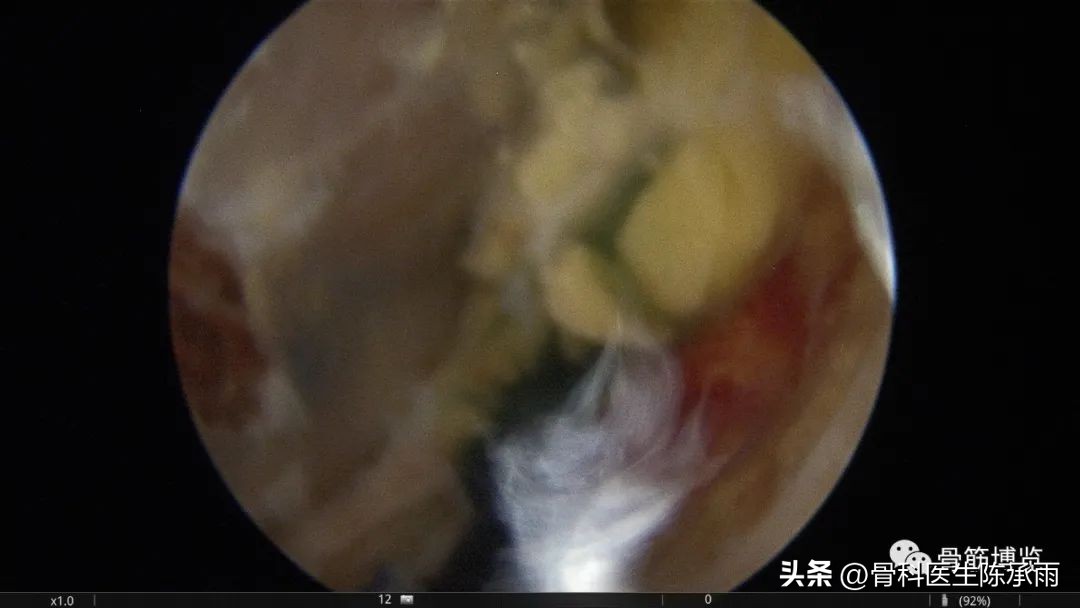

术中情况

关节腔探查,内侧半月板

同时建立低位后内侧入路,于高位观察,低位操作,术前囊腔内注入少量美兰以便于术中镜下显露囊腔,充分扩大内口切除可见的囊腔内壁。

镜下囊肿切除∶镜头进入后间室,膝关节放置"4"字位,探针探查腘窝囊肿与关节腔的交通口,通常位于腘窝囊肿前方后内侧关节囊皱襞上。通过后内侧入路用刨削器将后内侧关节囊皱襞清除,充分地扩大腓肠肌内侧头与半膜肌之间的交通口,并清理增生的束带组织,使得腘窝囊肿和关节腔之间的滑囊液可以双向流动。充分显露腓肠肌内侧头,可于腓肠肌内侧头与半膜肌之间暴露出腘窝囊肿,通过关节镜对腘窝囊肿进行关节腔内引流。将刨削器和关节镜伸入囊肿内部清理囊腔,屈曲膝关节至"4"字位,从外侧挤压囊肿位置,从而使囊壁更易切除。也可以在手术前向腘窝囊肿内注射亚甲蓝 2ml,可在镜下更好显示囊肿,完全切除亚甲蓝染色的囊壁、囊内分割部分和可能的多发性囊肿的囊壁。